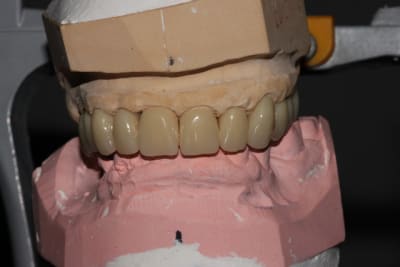

Du coup, pour finir:

-En janvier, c'est reparti: reprise de traitement 12 13 14. Comme je le disais, les RCR 15 16 sont en bon état, les endos asyptomatiques même si pas parfaites: je n'y ai pas touché, l'avenir me dira si j'ai eu raison.

Inlays-core 12 13 14, j'aurais pu réaliser des RCRs mais je ne me sentais pas de paralléliser les 9 piliers à l'oeil.

Le jour de l'empreinte des IC, on prend également une empreinte alginate du bridge pro en place.

Ainsi, par CFAO et en se basant sur les tissus mous périphériques, le labo nous a confectionné un duplicata du bridge pro en résine usinée, qui nous servira à enregistrer la RIM définitive: je n'aurai aucune retouche à y apporter.

Puis classique essayage d'armature (parfaite, merci le labo), et pose. Réglages occlusaux le lendemain.

Pano de contrôle (où je m'aperçois que j'avais laissé un morceau de Fuji entre 36 et 37, honte sur moi, d'où l'intérêt de la radio).

Photos de l'occlusion avant les réglages occlusaux, tout juste sorti du labo. J'ai diminué les contacts sur la 23 en entrée de cycle, et sur la 21 en incision. (bleu en statique, rouge en cycles masticatoires)